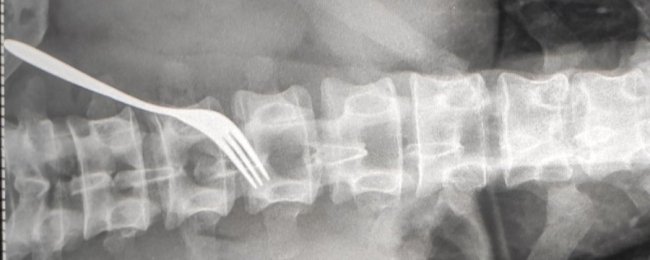

В Ужгороді чоловік жив з виделкою у шлунку три місяці. ФОТО

Виделку витягнули з чоловіка під час операції в Ужгородській міській клінічній лікарні. Хірургічне втручання провели 8 липня.

За словами медика, виделку пацієнт проковтнув 3-4 місяці тому: "Сталося це не гострим, а тупим кінцем. Це представник ромського населення. За 3-4 останні дні воно дуже спазмувало, подразнило слизову шлунку, тому вчора в нього були дуже різкі болі. Колеги були змушені брати його й оперувати. Забрали вилку і зашили стінку шлунку. Там є (у чоловіка, — ред.) порушена психіка".